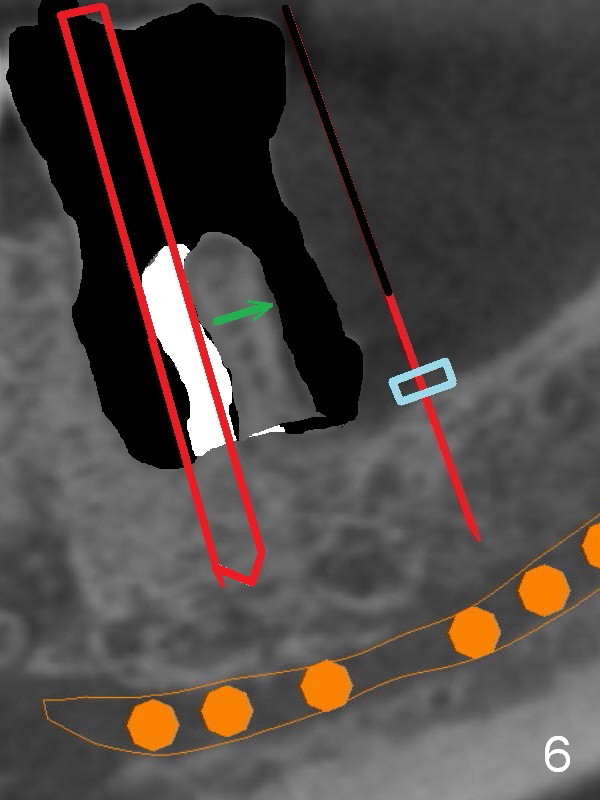

There is severe bone resorption around the distal root of the lower left 1st molar of the 56-year-old man (WG), while the loss of the 2nd molar is associated with limited bone height (Fig.1). A 5x14 mm implant will be placed at the mesial socket of #19 and 5.9 or 6.4x6 mm one is at the mesial site of #18 (Fig.7-9). Use a 2 mm pilot drill with 6 mm stopper from Sinus Master Kit (with extension) to initiate osteotomy at #18 immediately distal to the crown of #19, parallel to the long axis of the latter (Fig.2). After inserting a parallel pin at #18, extract the tooth #19 (Fig.3, antibiotic pending) and start osteotomy with a 2 mm pilot drill with 14 mm stopper (Fig.4). Insert the calibrated parallel pin at #19 (Fig.5) and measure the distance between the two parallel pins (approximately 10 mm, Fig.7). Sequential osteotomy and application of the Tatum taps (Fig.6 red rectangle) will push the septum distal (green arrow). As to #18 osteotomy, trephine, final and tap drills are to be used with control of the depth: 6 mm (Fig.7,9).